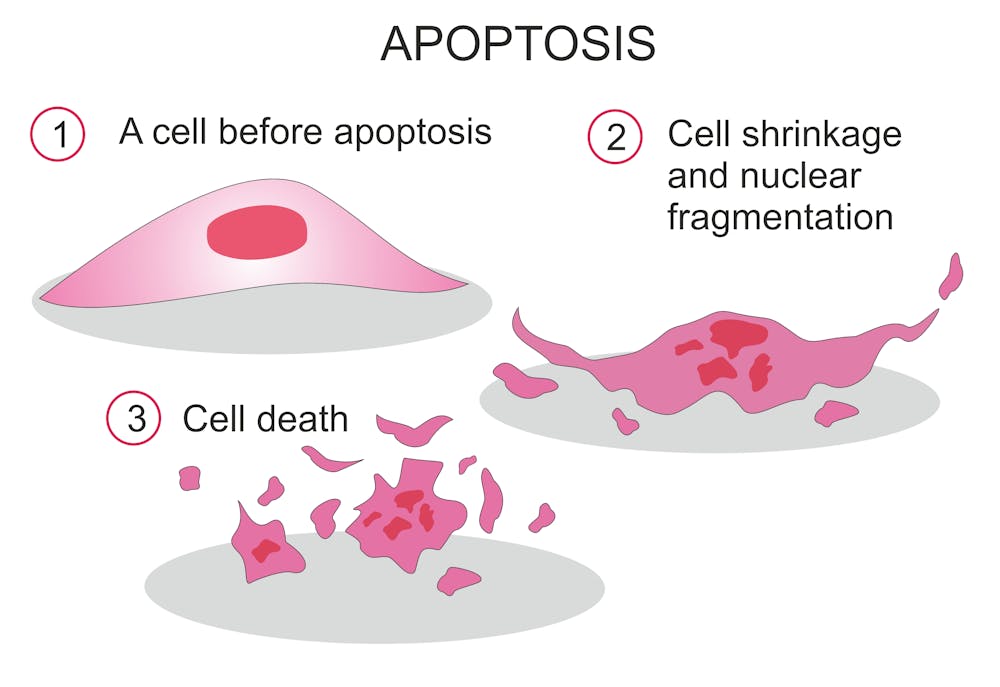

When the anthrax can’t grow anymore, it dies. Background in a review of treatment in the early days of antibiotics half a century ago, herman gold (1955) wrote: Published on april 29, 2023 medically reviewed by anju goel, md table of contents view all anthrax powder history how do humans encounter anthrax?

Antibiotics work in two main ways, by killing the anthrax or by stopping the anthrax from growing. For people who have been exposed to anthrax (but have no symptoms of the disease), providers may prescribe preventive.